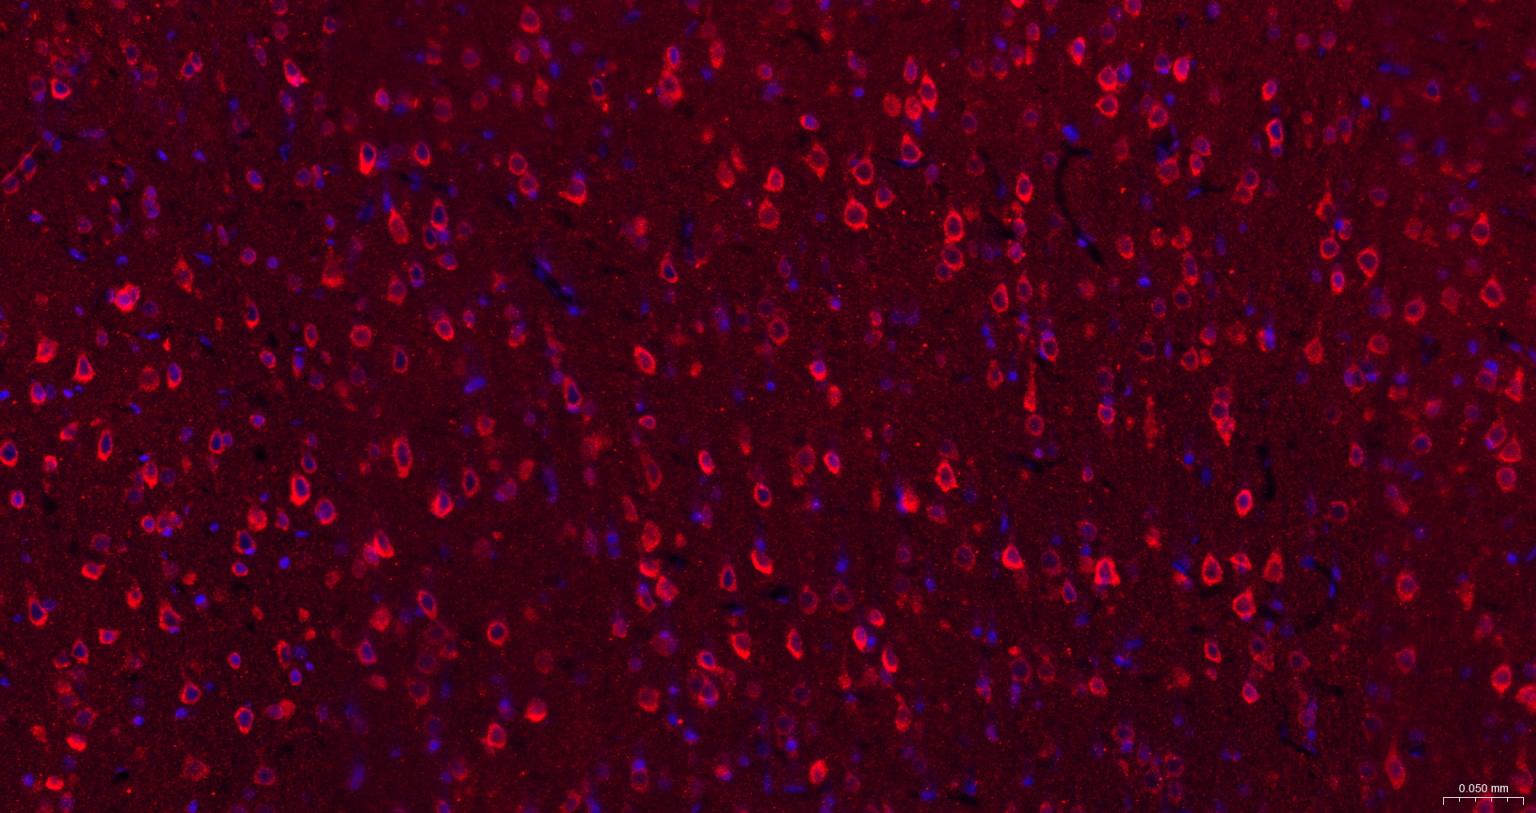

Paraformaldehyde-fixed, paraffin embedded Rat Cerebrum; Antigen retrieval by boiling in sodium citrate buffer (pH6.0) for 15 min; The section was incubated with IRE1 Polyclonal Antibody, Unconjugated (bs-8680R) at 1:200 overnight at 4°C. Followed by conjugated Goat Anti-Rabbit IgG antibody (Red, bs-0295G-BF594), DAPI (blue, C02-04002) was used to stain the cell nuclei.